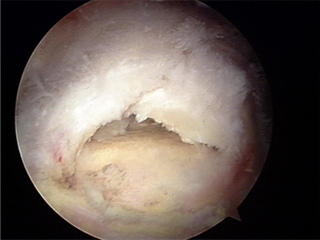

수술 전

x-ray 사진